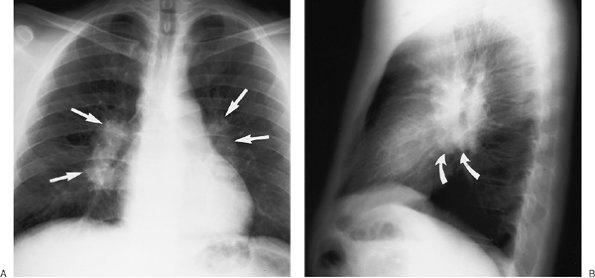

Sarcoidosis is a frequent cause of intrathoracic adenopathy in young adults. When multiple node groups are involved and adenopathy is symmetrically distributed in the hila and mediastinum in young asymptomatic adults, sarcoidosis is the likely cause. The hilar lymph nodes are frequently potato shaped and clear of the cardiac borders, a feature that is often useful in distinguishing sarcoidosis from lymphoma (Fig. 6-25).

Enlargement of paratracheal and bilateral hilar lymph nodes (the Garland triad, or the "1-2-3 sign") is a nonspecific pattern of adenopathy that is common in patients with sarcoidosis (Fig. 6-26).

FIGURE 6-25. Sarcoidosis. PA (A) and lateral (B) chest radiographs of an asymptomatic 25-year-old man show bilateral hilar adenopathy (straight arrows). The enlarged nodes are potato shaped and clear of the cardiac borders, a feature that can help distinguish them from lymphomatous enlargement of hilar nodes. On the lateral view, subcarinal adenopathy is also seen (curved arrows).